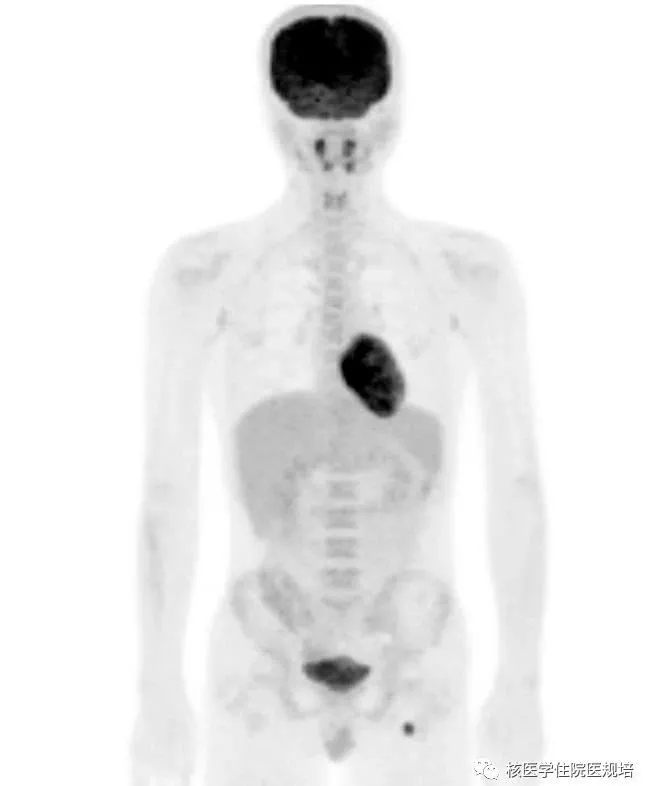

隔日再次行胸部 FDG PET/CT显像。显像前连续两餐进食低碳水化合物、高脂食物(第一餐为2只猪手,第二餐为5个茶叶蛋),第二餐4h后开始显像。与前次显像对照,除肿物显影外,左室其余心肌未见明显FDG摄取;前侧壁至心尖处占位表现为FDG摄取增高灶(SUVmax5.3),边界较清晰,范围约4.0×2.8×4.5cm,并侵犯乳头肌(图7)。

图7